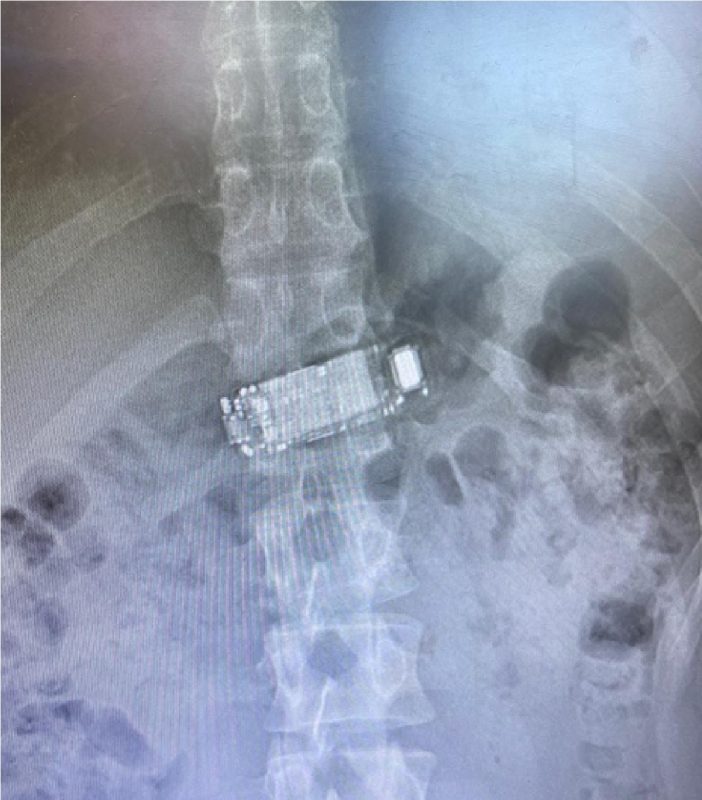

Raio-X mostra celular dentro do corpo do detento de Presídio Regional Raio-X mostra celular dentro do corpo do detento – Foto: Reprodução ND

Um caso inusitado foi registrado no Presídio Regional de Rio do Sul, no Alto Vale do Itajaí, na última quarta-feira (29). Um detento foi encaminhado ao hospital após engolir um celular. Ele precisou passar por um procedimento médico para que o aparelho fosse removido.

Segundo informações apuradas pela reportagem do ND Mais, o detento engoliu o celular após perceber que estava sendo monitorado. O aparelho teria sido jogado para dentro da galeria por um policial militar do Ctisp (Corpo Temporário de Inativos da Segurança Pública), que são policiais aposentados que voltam a ativa.